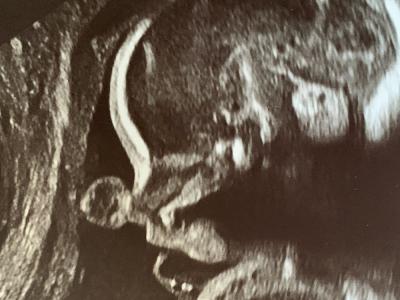

化石牙齿揭示人类进化数百万年来大脑在子

人类在26周时正在发育的大脑。资料来源:Tesla Monson(蜘蛛网eeook.com)据美国物...